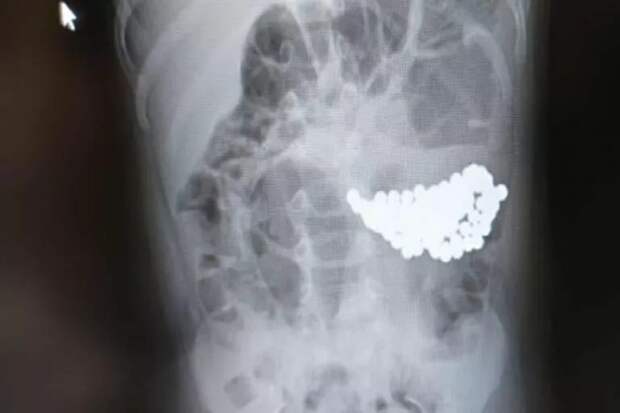

Последние невозможно обнаружить при рентген исследовании, что затрудняет диагностику, пишет «КП-Екатеринбург». Опасность представляют и резиновые игрушки, которые дети любят разрывать на мелкие части. Так, ранее сообщалось о двухлетнем ребенке, проглотившем 100 разноцветных магнитных шариков. Другой малыш играл с металлическим медальоном и случайно проглотил его.